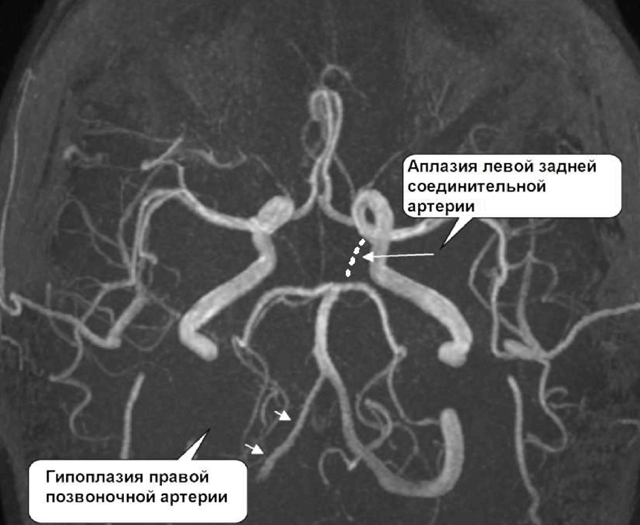

МР-ангіографія судин головного мозку — методика, яка полягає у візуалізації судин головного мозку при обстеженні, проведеному з використанням магнітно-резонансного томографа.

Цей метод ангіографії дає можливість візуалізації тонких зрізів судинної мережі, створення тривимірної схеми.

На отриманих проекціях фахівець бачить зображення судин всіх зон головного мозку. Він отримує можливість кровопостачання як всього головного мозку і його оболонок, так і окремих його структура, побачити патологічні зміни.

У ході процедури ангіографії лікар виявляє зміни в судинах тканин мозку, виявляє патології кровообігу в головному мозку та їх локалізацію. З допомогою МРА можлива не тільки діагностика патологій судин головного мозку, але і контроль результатів хірургічних втручань на судинах.

- артеріальні аномалії;

Фахівець оцінює картинку, яка зображує артерії і вени. Наявність рівних обрисів і рівномірного звуження просвітів, відсутність новоутворень, ознак кровотеч і скупчень рідини вважається нормою.

Якщо судини на ангиограмме зміщені, причина може бути в новоутвореннях, набряку мозку чи поганий відтік спинномозкової рідини. Вивчення мережі судин, що живить пухлину, дозволяє уточнити її розташування та оцінити допустимість хірургічного втручання.

При аневризмі стінка судини випинається або розширюється. Знімок дає можливість виміряти її параметри. Наявність атеросклеротичних бляшок, мальформації, спазму судини можна визначити по зміні діаметра судини або його просвіту.